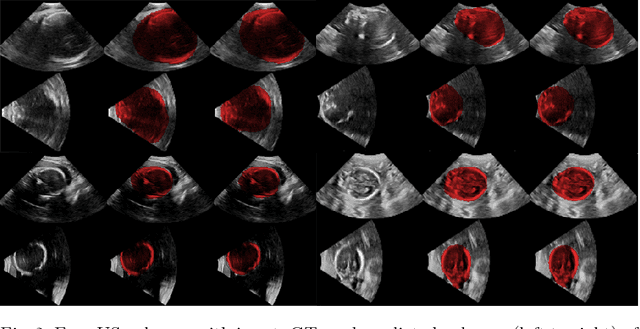

Abstract:Ultrasound (US) is the most widely used fetal imaging technique. However, US images have limited capture range, and suffer from view dependent artefacts such as acoustic shadows. Compounding of overlapping 3D US acquisitions into a high-resolution volume can extend the field of view and remove image artefacts, which is useful for retrospective analysis including population based studies. However, such volume reconstructions require information about relative transformations between probe positions from which the individual volumes were acquired. In prenatal US scans, the fetus can move independently from the mother, making external trackers such as electromagnetic or optical tracking unable to track the motion between probe position and the moving fetus. We provide a novel methodology for image-based tracking and volume reconstruction by combining recent advances in deep learning and simultaneous localisation and mapping (SLAM). Tracking semantics are established through the use of a Residual 3D U-Net and the output is fed to the SLAM algorithm. As a proof of concept, experiments are conducted on US volumes taken from a whole body fetal phantom, and from the heads of real fetuses. For the fetal head segmentation, we also introduce a novel weak annotation approach to minimise the required manual effort for ground truth annotation. We evaluate our method qualitatively, and quantitatively with respect to tissue discrimination accuracy and tracking robustness.